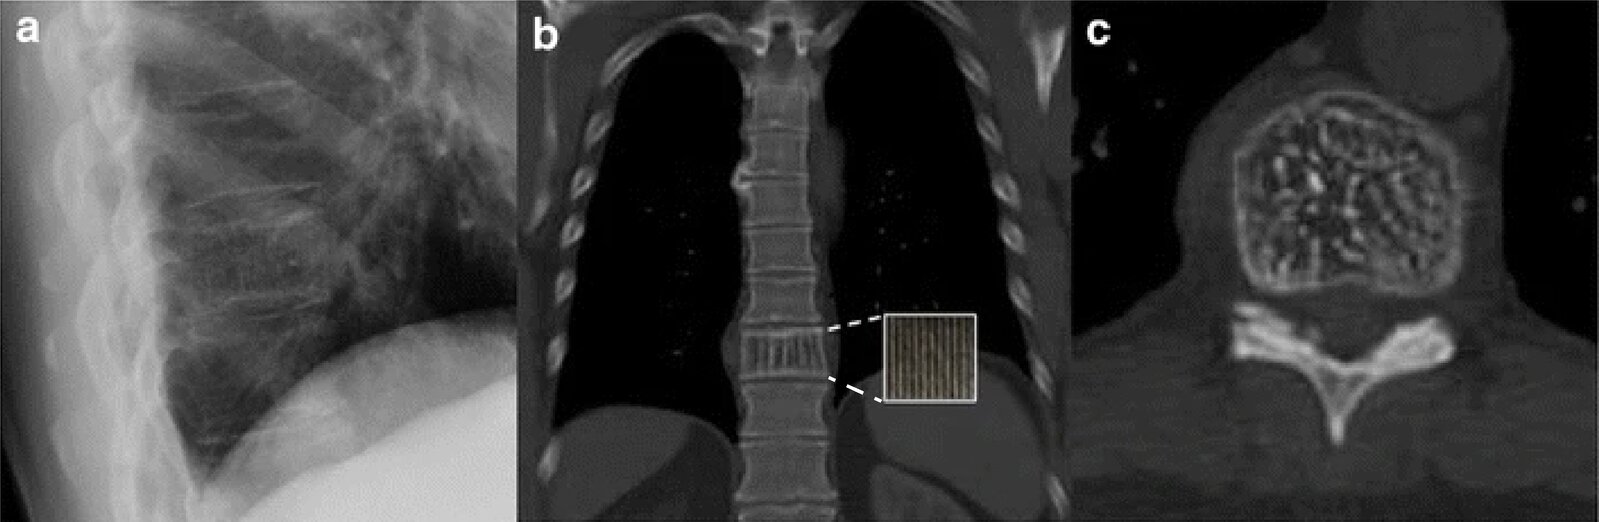

Intraosseous hemangioma

• Vascular neoplasm

• Peak incidence: 30–50 years

• Most common benign tumor of the spine

• Particularly involves the thoracic and lumbar vertebrae

• Possible complications: compression fractures, spinal stenosis, bleeding resulting in spinal epidural hematoma

• X-ray

• Vertically streaked vertebrae;

• Honeycomb appearance of lesions with definite margins

• Description: vascular neoplasm [10]

• Epidemiology

• Sex: ♂ < ♀ (1:2)

• Clinical features

• Most common benign tumor of the spine, particularly in the thoracic and lumbar vertebrae

• Usually asymptomatic; often an incidental finding

• Diagnostics: x-ray

• Vertical streaks visible in vertebrae

• Honeycomb appearance of lesion with sharp margins

• Treatment: usually no treatment required

• Complications

• Compression fractures

• Spinal stenosis

• Bleeding with subsequent spinal epidural hematoma